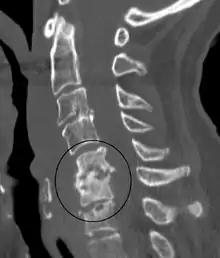

| Discitis in a 2 year old child. | |

Diagnosis is usually apparent on MRI, although plain X-rays and CT examinations can be suggestive. The MRI will reveal air changes in the disc and possibly even external involvement involving the bone or epidural regions. A biopsy may be performed and helps with diagnosis in some cases but often an organism is not obtained. C-reactive protein levels and ESR levels will be elevated and are useful for treatment. Often, the white blood cell count will be normal and the patient will be afebrile.